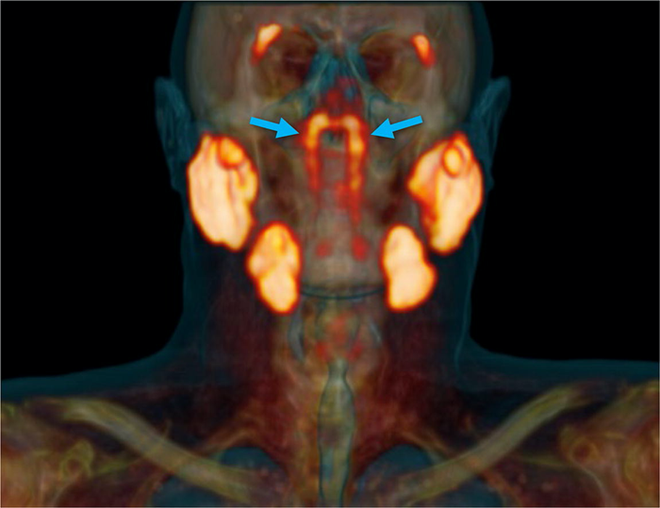

Vogel là một nhà ung thư học, khi đang cùng nhóm nghiên cứu của mình quét cơ thể những bệnh nhân ung thư tuyến tiền liệt bằng PSMA PET/CT, một kỹ thuật chụp ảnh cơ thể tiên tiến nhất hiện nay nhằm tìm ra những khối u di căn, ông đột nhiên phát hiện một "thực thế không xác định" nằm phía sau mũi, trên vòm miệng và gần với tâm đầu của bệnh nhân.

Ban đầu, họ chỉ cho rằng đó là một cấu trúc giải phẫu cá biệt của bệnh nhân ung thư này. Tuy nhiên, sau khi kiểm tra toàn bộ ảnh chụp PSMA PET/CT của 100 bệnh nhân trong đợt kiểm tra, Vogel bất ngờ thấy tất cả họ đều có những mô hình ống này, với ống dẫn lưu có thể nhìn thấy về phía vách mũi họng.

Các công nghệ chụp ảnh y tế cũ như siêu âm, chụp cắt lớp CT hay thậm chí cộng hưởng từ MRI đều không đủ độ phân giải hoặc đủ nhạy để phát hiện ra tuyến nước bọt mới. Phải đến tận bây giờ, khi PSMA-PET/CT, một công nghệ chụp ảnh y tế tiên tiến nhất dành cho bệnh nhân ung thư sử dụng chất huỳnh quang phát xạ, mới vô tình làm được điều đó.